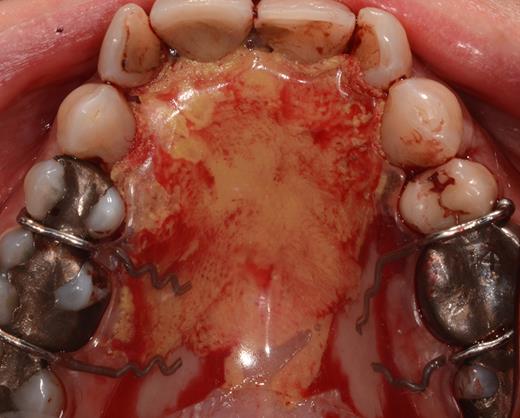

After a sulcular incision on the palatal side from teeth 15 to 25 and an incision in the midline of the palate omitting the incisive papilla and the two orifices of the NPD, two full-thickness mucoperiosteal flaps were raised. Thereafter, the incisive papilla and the whole contents of the incisive canal were enucleated (Figs 4–6). The bony incisive canal was filled with autologous bone harvested from the palatal region (bone scraper) (Fig. 7). A tension-free primary wound closure was achieved by moving the palatal flaps to the midline using single button and interdental vertical mattress sutures (Monocryl 4-0, Ethicon, Johnson & Johnson, USA) (Fig. 8). To avoid wound dehiscence and hematoma, an iodoforme gauze and a palatal plate were applied (Fig. 9). The patient was instructed to rinse three times a day with 0.1% chlorhexidine (formula hospitalis) for 2 weeks postoperatively. Sutures were removed after 14 days.

Situation after removal of the entire soft tissue contents of the incisive canal.